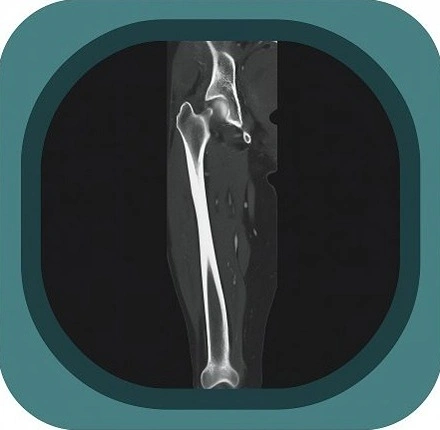

Explore full-body CT anatomy in 3 planes. Our high-resolution, carefully labelled images reveal micro-anatomy—ideal for radiologists, radiographers and surgeons.